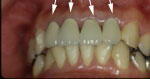

6.6年後

|

中央の2本は吸収が急速に進み、

右側の歯は、ゆっくりと進み

左の歯は、無事です。

同じ条件でも、経過は様々です。 |